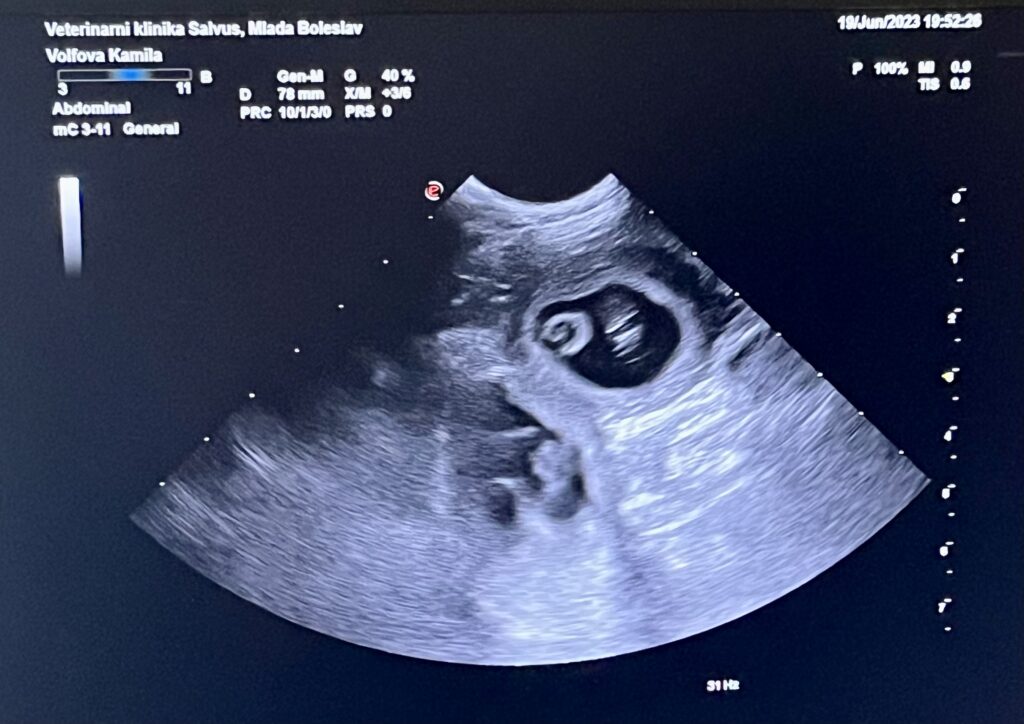

Předpokládaný termín porodu je 23.7.2023